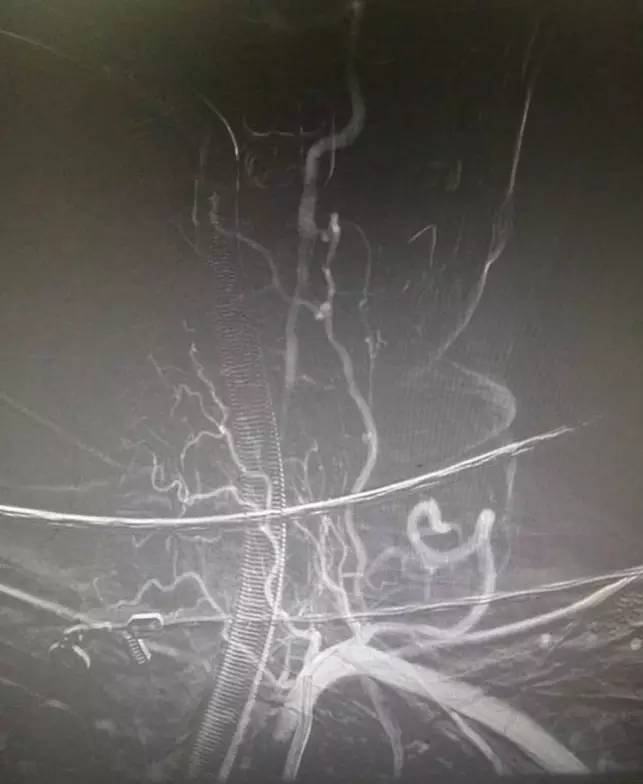

接到会诊通知,结合患者症状考虑椎基底动脉病变,未静脉溶栓直接进导管室造影,结果如下。

▼左锁骨下动脉造影显示左椎动脉闭塞,椎动脉V3段通过肌支代偿见返流。

▼右椎动脉造影见基底动脉末端闭塞。双侧颈内动脉造影无殊,双侧后交通未见显影。

问题焦点是左椎动脉是否是急性闭塞,这直接决定开通策略不同:如果是急性闭塞那么先开通左椎再开通基底,如果不是那么就直接开通基底。根据片子很难准确判断左椎是否是急性闭塞,纠结后决定直接去开通基底:椎动脉长段闭塞而且肌支代偿很好,应该是陈旧性闭塞可能大,尽快开通基底为患者争夺时间。

▼支架释放后,右大脑后及小脑上显影同时看到基底动脉的血栓,拉栓一次就再通。

此时手术是否结束?内心又开始纠结了,贪心的本性又暴露,如果左椎是急性闭塞那么打通之后给患者又多加一个保险,这样以后万一右椎有什么三长两短那么左椎还可以救命所以决定开通左椎:费了好大劲通过微导丝进入椎开口内,向上不能通过闭塞段考虑为陈旧性闭塞,遂即放弃开通!术后欣慰宁维持!